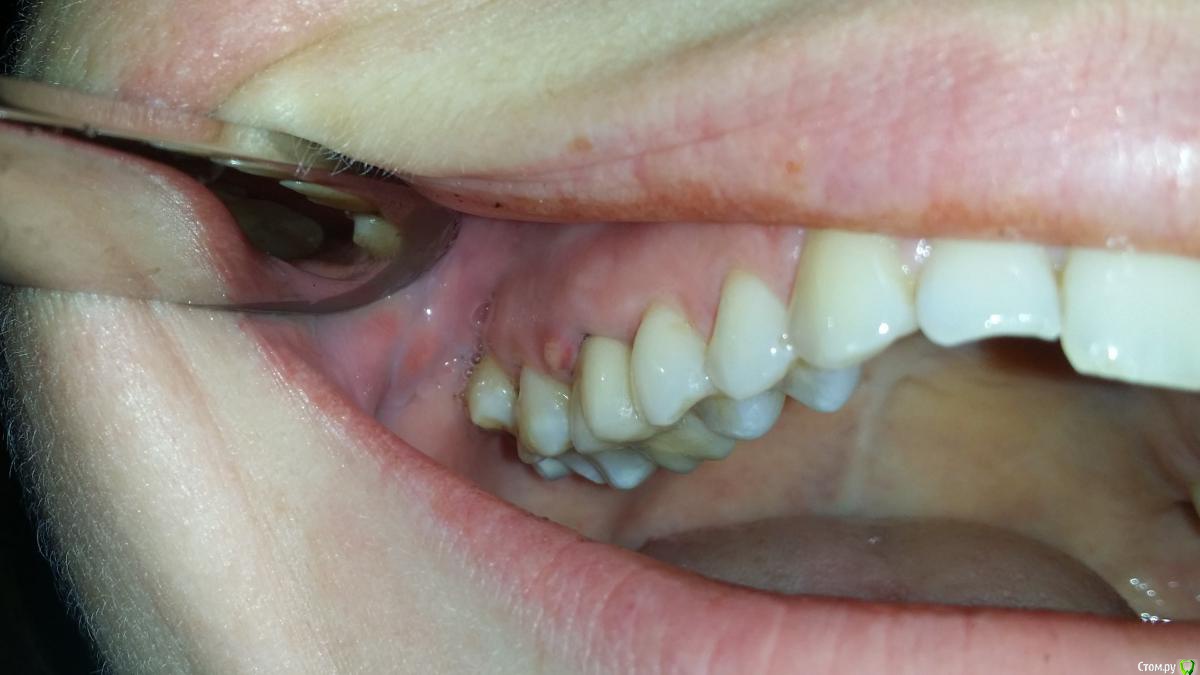

СветланаАндревна Опубликовано 26 октября, 2015 Поделиться Опубликовано 26 октября, 2015 (изменено) Здравствуйте! Сейчас нахожусь не в России, Великобритания.Кратко так. Речь о шестерке сверху справа. Где-то в 2000г депульпировали зуб, в 2005 поставили штифт и на нем слепили что-то похожее на зуб (по высоте был меньше, чем зубной ряд), в 2010 поставили коронку. Но как-то неудачно, в 2011 воспалилась десна, ее разрезали, почистили (налет?!), зашили, вроде более менее стоял. Последний год что-то не так с десной было, то ли чесалась, то ли что, какой-то дискомфорт, но толково врачу объяснить не смогла. Попросила на всякий случай рентген, посмотреть, не гниет ли под коронкой. Врач отказал, обосновав тем, что пока не снимем коронку не увидим что там. А десна немного воспалена, из-за того, что прилегающие 5 и 7 на контакте кариозные. Кариес пролечили, и я уехала в Британию. Через неделю десна воспалилась, и вылез гнойник. Пошли к местному стоматологу. Выписали антибиотик (амоксициллин?! вроде). Пропив, чуть полегчало, еще полоскала фурацилином. Приобрели ирригатор, с дуру еще им промывать стала. Опять вылезли гнойники. Сегодня наконец удалось опять к стоматологу попасть, говорит,раз антибиотик не помог, значит надо удалять. Попросила сделать рентген. Его и прилагаю. Плюс фото десны с гнойником Можно ли спасти зуб? Или все? Планирую ехать в Россию, попытаться спасти зуб, если это возможно. Сколько времени это может занять? пысы. Ситуация осложнена тем, что у меня ребенок маленький, придется оставить его папе на время поездки, а у него отпуск не резиновый. С собой брать не вариант, и дороже обойдется, и оставлять его в России некому пока я на прием к врачу ходить буду.. Изменено 26 октября, 2015 пользователем СветланаАндревна Ссылка на комментарий

СветланаАндревна Опубликовано 26 октября, 2015 Автор Поделиться Опубликовано 26 октября, 2015 Так дело не в десне? Из-за корня? Местный врач обмолвился, что может направить к ортодонту, он каналы перепломбирует, возможно, это может помочь. Но что-то отзывы о местных стоматологах в целом не вызывают доверия, к этому прибавить стоимость, и мысль о лечении на месте меня в уныние приводит. Ссылка на комментарий

СветланаАндревна Опубликовано 7 ноября, 2015 Автор Поделиться Опубликовано 7 ноября, 2015 Здравствуйте.Сходила я на консультацию к двум стомотологам в Питере.Первый врач сказал предворительно(еще не видел еще томографию), что если лечить, то минимум полгода. То есть раз в месяц придется приезжать менять лекарство в корнях. Но его совет, не мучаться, а удалить и ставить имплант. Второй сразу сказал, удалять, не посмотрев снимки. Аргументируя тем, что раз свищ, то и киста должно быть большая, и воспалению не год, а лет 8, и мороки с зубом будет много, а вот получиться спасти зуб, под большим вопросом. Кстати сказать, первый врач эндодонт, второй - ортопед.оВопрос, что реально это полгода лечить зуб? Врач сказал, что свищ то быстро затянется, а воспление не скоро пройдет. И ортопед говорит, что хирург будет вырывать зуб, а потом чистить еще. Мне казалось, просто выдрать достаточно будет... Ссылка на комментарий